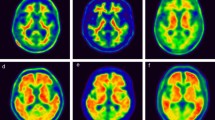

Visual interpretation

The PiB PET images generated through the QC process above were independently interpreted visually by three expert raters blinded to the clinical category. Information about age, sex, and T1-weighted MRI images was provided to the raters. In the visual interpretation, the raters evaluated the regional PiB uptake for each of four cortical areas on each side (frontal lobe, lateral temporal lobe, lateral parietal lobe, and precuneus/posterior cingulate gyrus) as positive, equivocal, or negative regional uptake, the definitions of which were as follows: positive, uptake is clearly higher than in cerebral white matter that covers more than one gyrus of the cerebral cortical area; equivocal, uptake is slightly higher than or similar to that in cerebral white matter that covers more than one gyrus of the cerebral cortical area, i.e., radioactivity extending beyond white matter to the cortical surface, or a high uptake spot limited to one gyrus; and negative, uptake is lower than in cerebral white matter in any region of the cerebral cortex. Of the total scans in J-ADNI, 91.3% of the visual assessments were matched among the three raters (Cohen kappa = 0.88). After independent interpretations, consensus reading was performed to determine the unified visual interpretation for each PET image by the three raters and two other experienced discussants [10]. The unified visual interpretation stored in the J-ADNI was used for this study.

Figure 2 shows the time courses of SUVRs grouped by visual assessment and by clinical category. In the amyloid-negative CN group, the upper confidence limit of the 97.5 percentile for the baseline SUVR was 1.20. Most SUVRs in the amyloid-negative group (LMCI, ADD) remained below this level. In the amyloid-equivocal group, no evident differences in the longitudinal trends of SUVR were observed among the CN, LMCI, and ADD groups. In the amyloid-positive group, all individual values remained above SUVR 1.3, indicating a clear difference in the distribution of the SUVR between the amyloid-positive and amyloid-negative groups. In the visually amyloid-positive group, the annual changes in the SUVR were 0.04 ± 0.04 in the CN group, 0.04 ± 0.07 in the LMCI group, and 0.03 ± 0.07 in the ADD group. The SUVRs in the amyloid-positive CN group tended to increase over time from a lower baseline SUVR compared with the LMCI and ADD groups. Conversely, no evident differences in the longitudinal trends of SUVR were observed among the LMCI and ADD groups. In the visually amyloid-positive group, 19 individuals showed a decreasing SUVR (CN n = 1, LMCI n = 8, ADD n = 10). The baseline SUVR in these individuals was significantly higher than the baseline SUVR of all visually amyloid-positive individuals (2.10 ± 0.33 vs 1.86 ± 0.31, p = 0.003).

Individual longitudinal changes in SUVR during the 3-year follow-up. Scatterplots show the SUVR at baseline and in the 3-year follow-up. The dotted line shows the SUVR threshold of 1.20 derived from the upper confidence limit of the 97.5 percentile for the baseline SUVR in the amyloid-negative CN group. Negative PiB visually amyloid-negative, Equivocal PiB visually equivocal, Positive PiB visually amyloid-positive, ΔSUVR the annual change in the SUVR

In individuals evaluated as visually amyloid-negative, their SUVRs remained within the 97.5 percentile of the baseline SUVR over time. This finding was observed regardless of the clinical categories of CN, LMCI, and ADD (Fig. 2). Barring a few exceptions, individuals with an amyloid-negative image showed no trend towards a gradual increase in the SUVR. In the amyloid-negative group, very few individuals showed an upward trend in the SUVR. Similar cases have been found in other longitudinal cohorts [4, 35], suggesting that they may represent the very early stage when amyloid accumulation has turned upward. On the other hand, individuals with a visually amyloid-positive image showed a time course with an SUVR of 1.3 or higher. The SUVR in the visually amyloid-positive group showed a gradual increase with a few exceptions. This was consistent with previous studies that reported [4,5,6,7, 36, 37] that when a cut-off value of SUVR or distribution volume ratio dividing low and high accumulation was used, the high accumulation group showed a gradual increasing tendency above the cut-off value, and the low accumulation group did not show an increasing tendency under the cut-off value. These findings suggest that the risk of progression of amyloid accumulation is low in the visually-negative group, whereas the visually-positive group is at an increased risk as well as SUVRs.